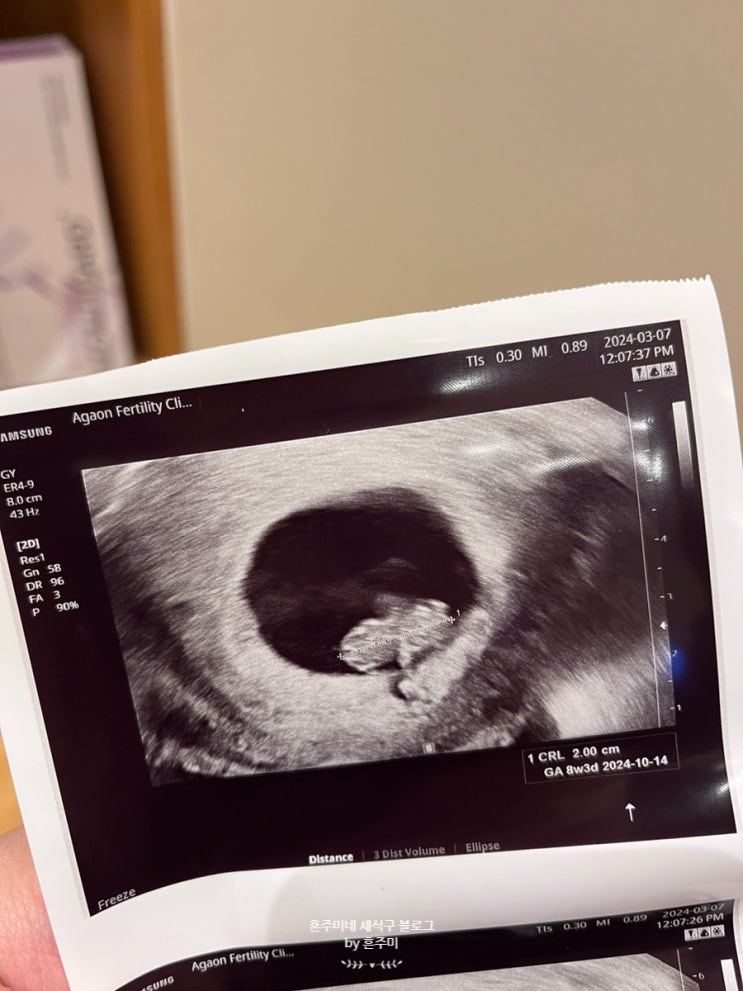

둘째 임신 5주~8주 증상기록 * 금천구 보건소 임산부 등록

지난번 둘찌 임밍아웃해두고.. 시간이 또 휘리릭 가버렸네유 ㅋㅋ 첫찌때만큼 자세하게는 못 쓰겠지만 둘찌...

[둘째 임신일기 9주-13주] 태아 심장소리 성별 구분가능..?

둘찌야 어서와라 했던 시간이 무색하게 벌써 15주차..ㅎㅎ 둘째 임신일기 9주-13주 기록해야지 :) [ 3/13 -...